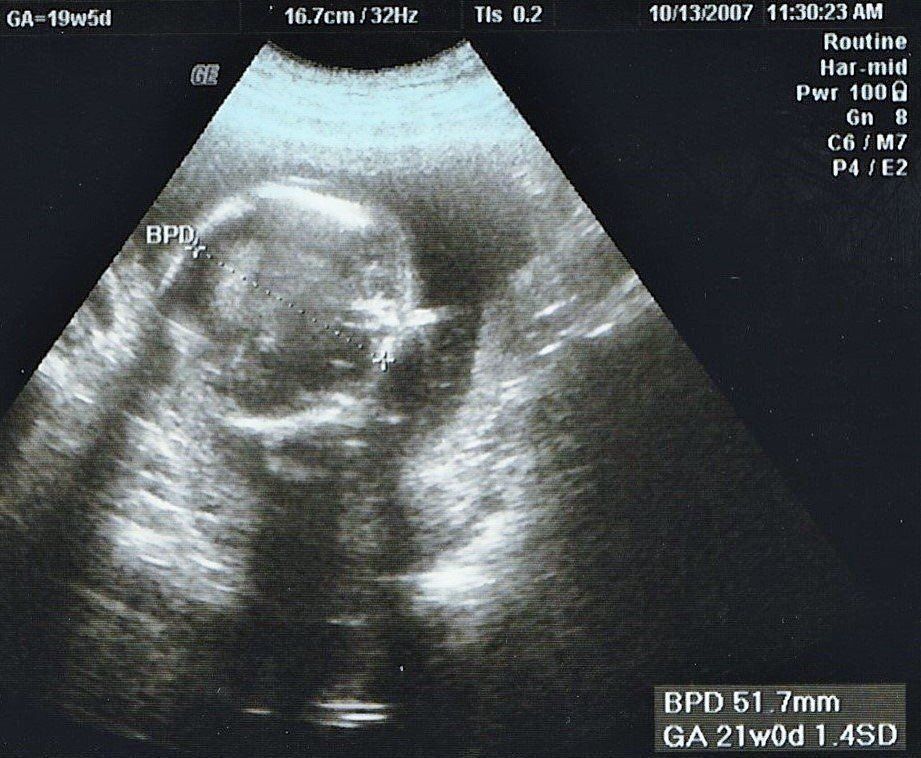

妊娠19週目のエコー写真

安定期に入り、検診のたびに体重や血圧を測るようになりました。前回の検診時から、8~10kgの増加が目安と言われていましたが、妊娠15週から19週の間ですでに1.3kg増。強い食欲と眠気に勝てない毎日に危機感が募り、マタニティーヨガ、マタニティービクスを開始しました。